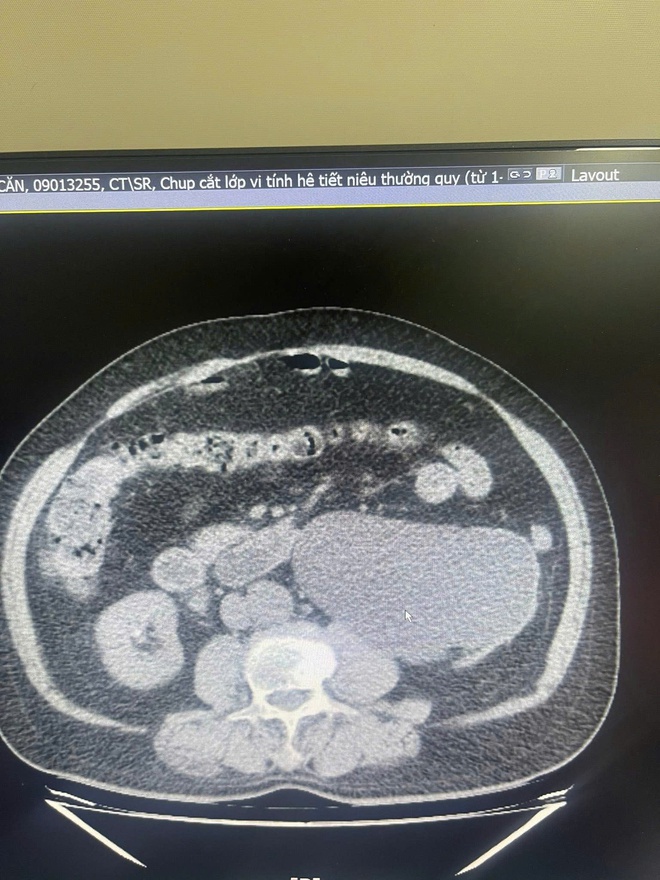

"Sỏi đường tiết niệu nếu không được phát hiện và điều trị kịp thời sẽ gây tắc nghẽn kéo dài. Hậu quả là nước tiểu bị ứ đọng gây giãn đài bể thận, ứ nước độ 3, độ 4. Môi trường nước tiểu ứ đọng là điều kiện lý tưởng cho vi khuẩn phát triển, dẫn đến nhiễm trùng tiết niệu tái diễn, viêm thận bể thận"- bác sĩ Long phân tích.

Khi tình trạng tắc nghẽn và viêm nhiễm kéo dài âm thầm, nhu mô thận sẽ mỏng dần và mất chức năng lọc máu. Đến giai đoạn cuối, khi thận đã trở thành một túi nước nhiễm trùng hoặc xơ teo, các bác sĩ buộc phải chỉ định cắt bỏ thận để ngăn chặn nguy cơ nhiễm trùng huyết, bảo toàn tính mạng cho người bệnh.